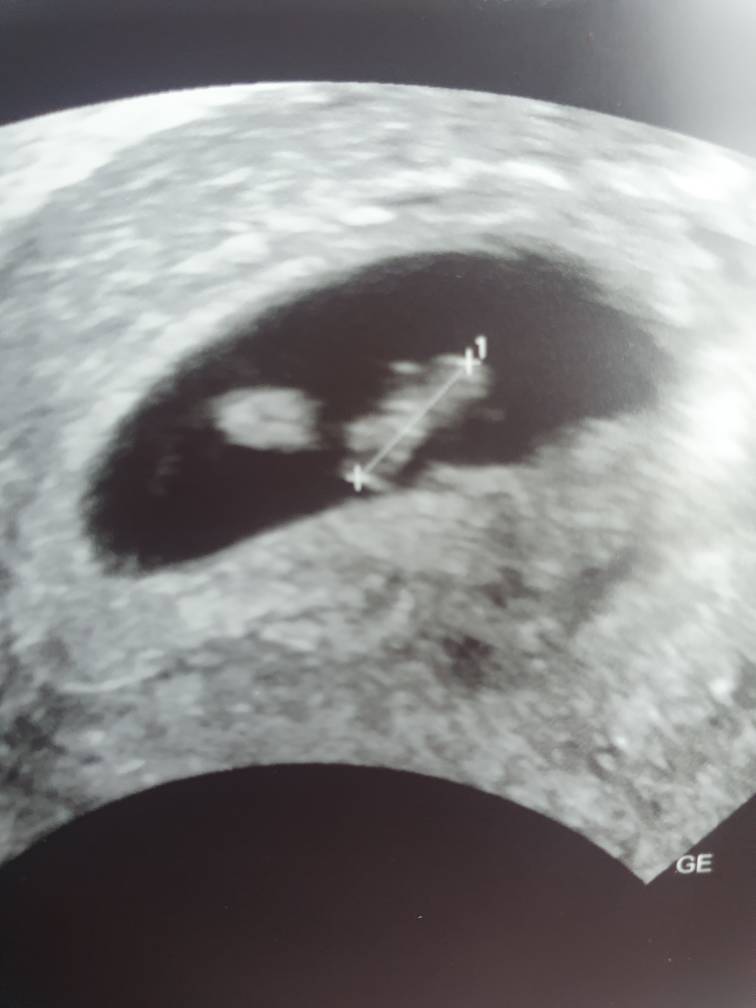

Dziewczyny jestem po wizycie i jestem w totalnym szoku tak samo jak mój lekarz . Nie wiem co mam wgl myśleć . Według OM 7 tydzień ale UGG się nie pokrywa na tym etapie już. Są trzy pecherzyki z ciałkiem żółtym bez zarodka . Jestem w szoku . Powiedział mi ze ciężko mu to zinterpretować bo na codzień się to nie zdążą . Może być tak ze pojawia się 3 zarodki , 2 , 1 lub wgl nic z tego nie bedzie . Nie wiem co mam powiedzieć nawet . Wizyta za tydzień .

Wrzucam zdjęcie fasolki[emoji846]